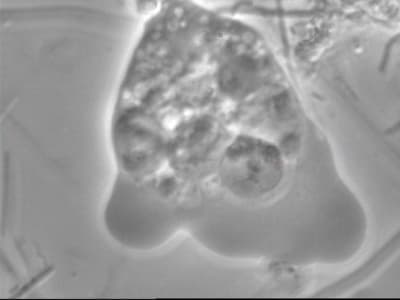

un trichomonas.

une entamoeba

la boule noire qui se déplace et se déforme je ne sais pas trop

peut être kyste amibien

Encore quelques photos:

Une amibe qui boulote un globule bien vivant. A noter que le globule en haut du cliché était bien circulaire et vivant (les petits "granulés" bougent dans tous les sens) 1 minute avant l'agression